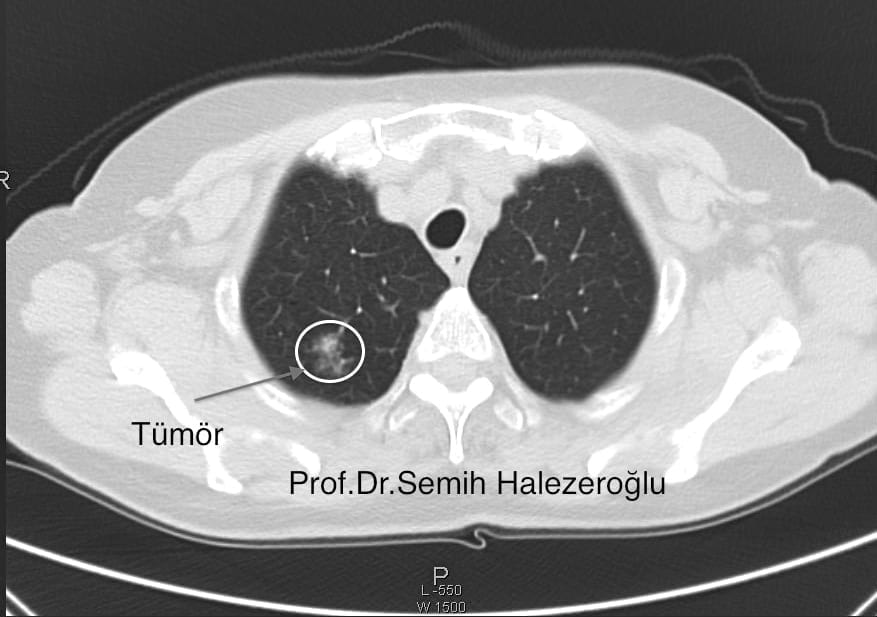

Her tomografi çektiren kanser olur mu. Bunda kanser olma riski vardır. ülkemizde her yıl binlerce yeni kanser tanısı konuluyor ve bu oran her yıl giderek artıyor. Tomografi kanser riskini biraz arttırıyor olabilir ama bunlara dikkat eden kişinin aynı zamanda güneyde güneş altında elinde sigarası ile saatlerce yatmayan çocuğuna sık sık hamburger patates yedirmeyen. Kanser belirtilerini nasıl anlarız.

Mustafa menteş görüntülü yanıtlıyor. Bor a göre görüntüleme yöntemlerindeki radyasyonun yarattığı kanser riski sigara ve diğer nedenlerdan. Bir tomografi çekimi sırasında 15 saniye içerisinde 12 milisievert msv radyasyon alırsınız. Ancak her tomografi çektiren insan kanser olacak demek değildir.

Tomografinin sağlığa büyük zararı var. Tedavi edici bir yönü bulunmamaktadır. Sizin kromozomlarınıza zarar verme riski vardır. Gereksiz yere sürekli tomografi çektiren insanlarda bu ışınlara fazlasıyla maruz kalınması nedeniyle kanser belirtileri gözlenebiliyor.

Vücuda radyasyon yayan bu uygulama mutlaka gerektiği zaman çekilmelidir. Peki kanserin belirtileri biliniyor mu. Kanser olma ihtimalini artırır sadece. Radyasyona maruz kaldığı doğru ama direkt tomografi çektiren kanserdir diyemeyiz.